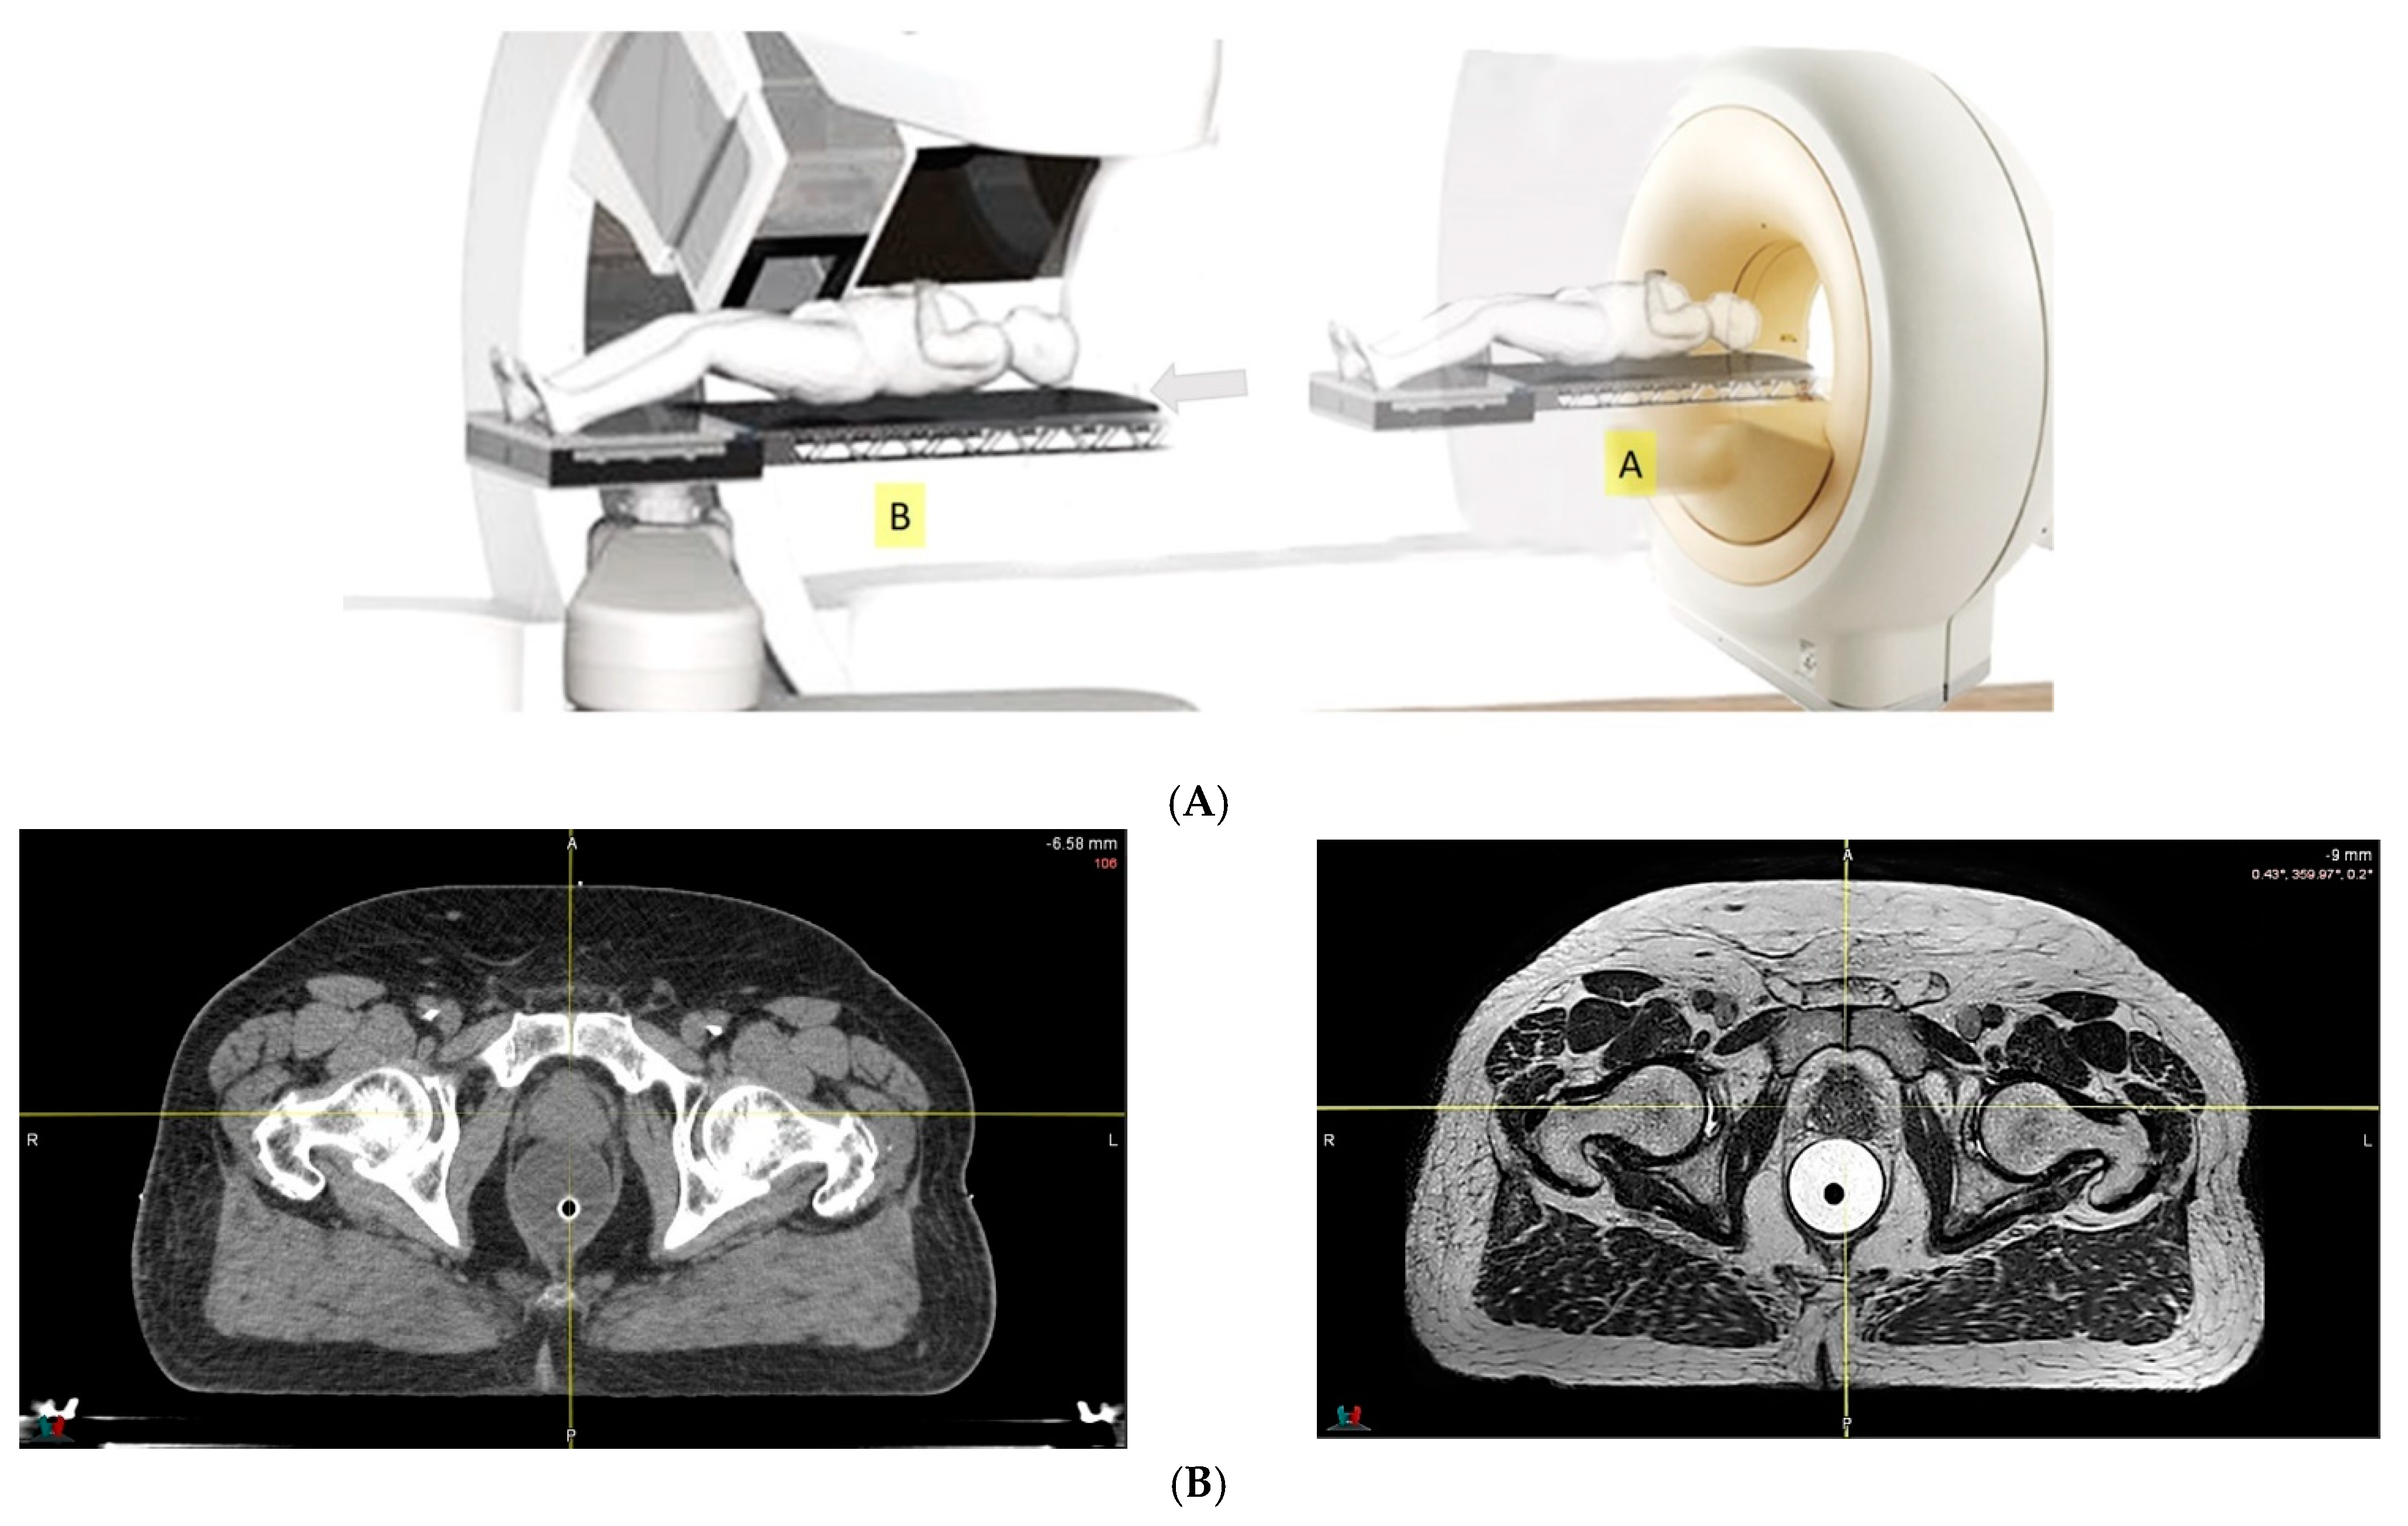

- Because of the inferior soft tissue contrast, orthogonal X-ray imaging systems rely on bony structures for verification of treatment position during patient setup. This type of setup technique can result in large positioning errors due to daily movement of the target and organs at risk (OARs) relative to the bony structures in the former technique. With fiducial markers implanted inside the prostate, many studies concluded that image registration by fiducial markers would reduce matching error. However, some patients may not accept marker implantation. Migration of markers with time may introduce registration errors. Such problems can now be minimized using on-board cone beam CT (CBCT). The better image quality of CBCT can provide 3D images and more information on the anatomic relationships between organs [64,65], which can be used to improve the accuracy of patient setup. Besides patient positioning, CBCT images can also provide information about inter-fractional changes in patient anatomy. In a recent study, an image-based correction method to generate pseudo-CT images from CBCT images was investigated for possible application in proton dose calculations [66] in adaptive PT. MRI, which has the ability to offer fast real-time imaging with high soft tissue contrast in the absence of ionizing radiation exposure [67], is being investigated for use in patient setup in RT. Our study using an external MRI setup room [68] and studies by others [69] indicated that patient positioning accuracy on the order of 1 mm is feasible, and is a significant reduction from that of conventional setup systems.